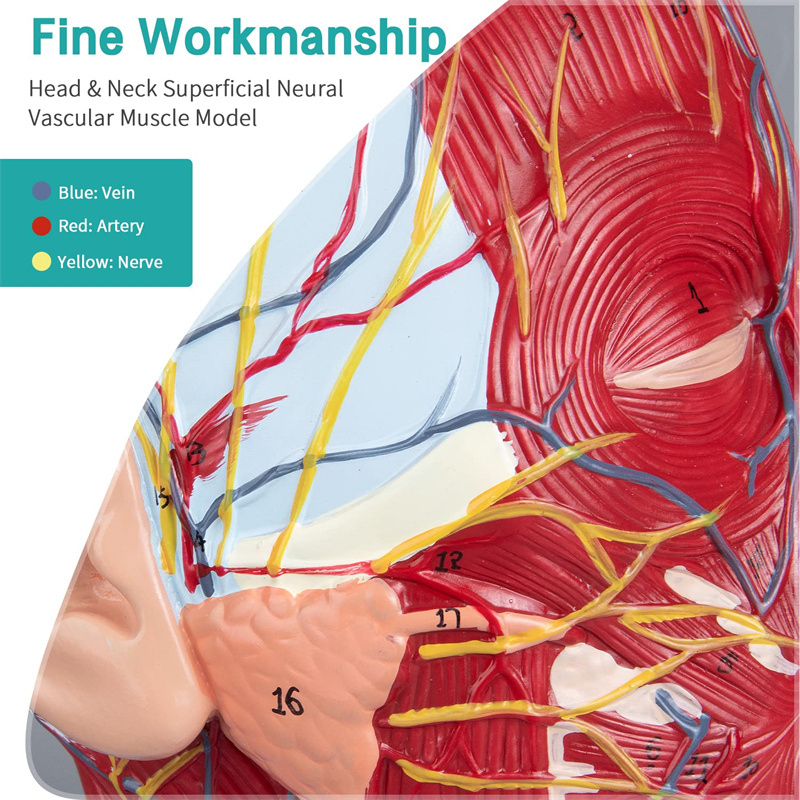

【Superficial Neurovascular Muscle Model】Highly detailed, numbers marked, detachable ear, deepen the understanding of the superficial muscles, vessels, nerves and the internal structures of the head & neck. Red-artery, blue-vein, yellow-nerve.

【Features】It shows the superficial muscles of the exposed face; the superficial blood vessels & nerves of the face & scalp; the inner structures of parotid gland & upper respiratory tract; the sagittal cross-section structure of the cervical spine.

This model shows details of the right head neck and mid sagittal section of the human. including the superficial

muscles of the exposed face; the superficial blood vessels and nerves of the face and scalp; the inner structures

of parotid gland and upper respiratory tract; the sagittal cross-section structure of the cervical spine.

This model is a natural large head and neck superficial neurovascular muscle model, 1 component, showing the details of the human right head and neck and median sagittal section, including the exposed superficial muscles of the face, superficial vessels of the face and scalp, nerves and the medial structure of the parotid gland and upper respiratory tract, and the sagittal section structure of the cervical spine